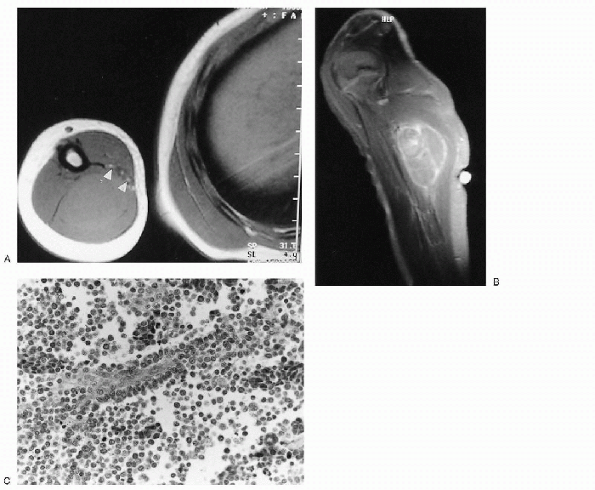

Figure 23-18 Alveolar rhabdomyosarcoma. (A)

Axial T1-weighted magnetic resonance image through the humerus shows a slightly hyperintense mass replacing the triceps muscles of the arm. The neurovascular bundle (arrowheads) is contiguous with the anterior medial edge of the mass. (B) After contrast administration, there is heterogeneous enhancement of the mass. (C) Photomicrograph of the lesion demonstrates undifferentiated small blue cells lining fibrovascular septae with central discohesion, imparting an alveolar appearance. |

Embryonal rhabdomyosarcoma consists of poorly differentiated rhabdomyoblasts with a limited collagen matrix.

□ The rhabdomyoblasts are small,

eosinophilic cytoplasm (see Fig. 23-18C).

Alveolar rhabdomyosarcoma is composed of

poorly differentiated small, round-to-oval tumor cells that show

spaces.-

□ The individual cellular aggregates are separated and surrounded by irregularly shaped fibrous trabeculae.